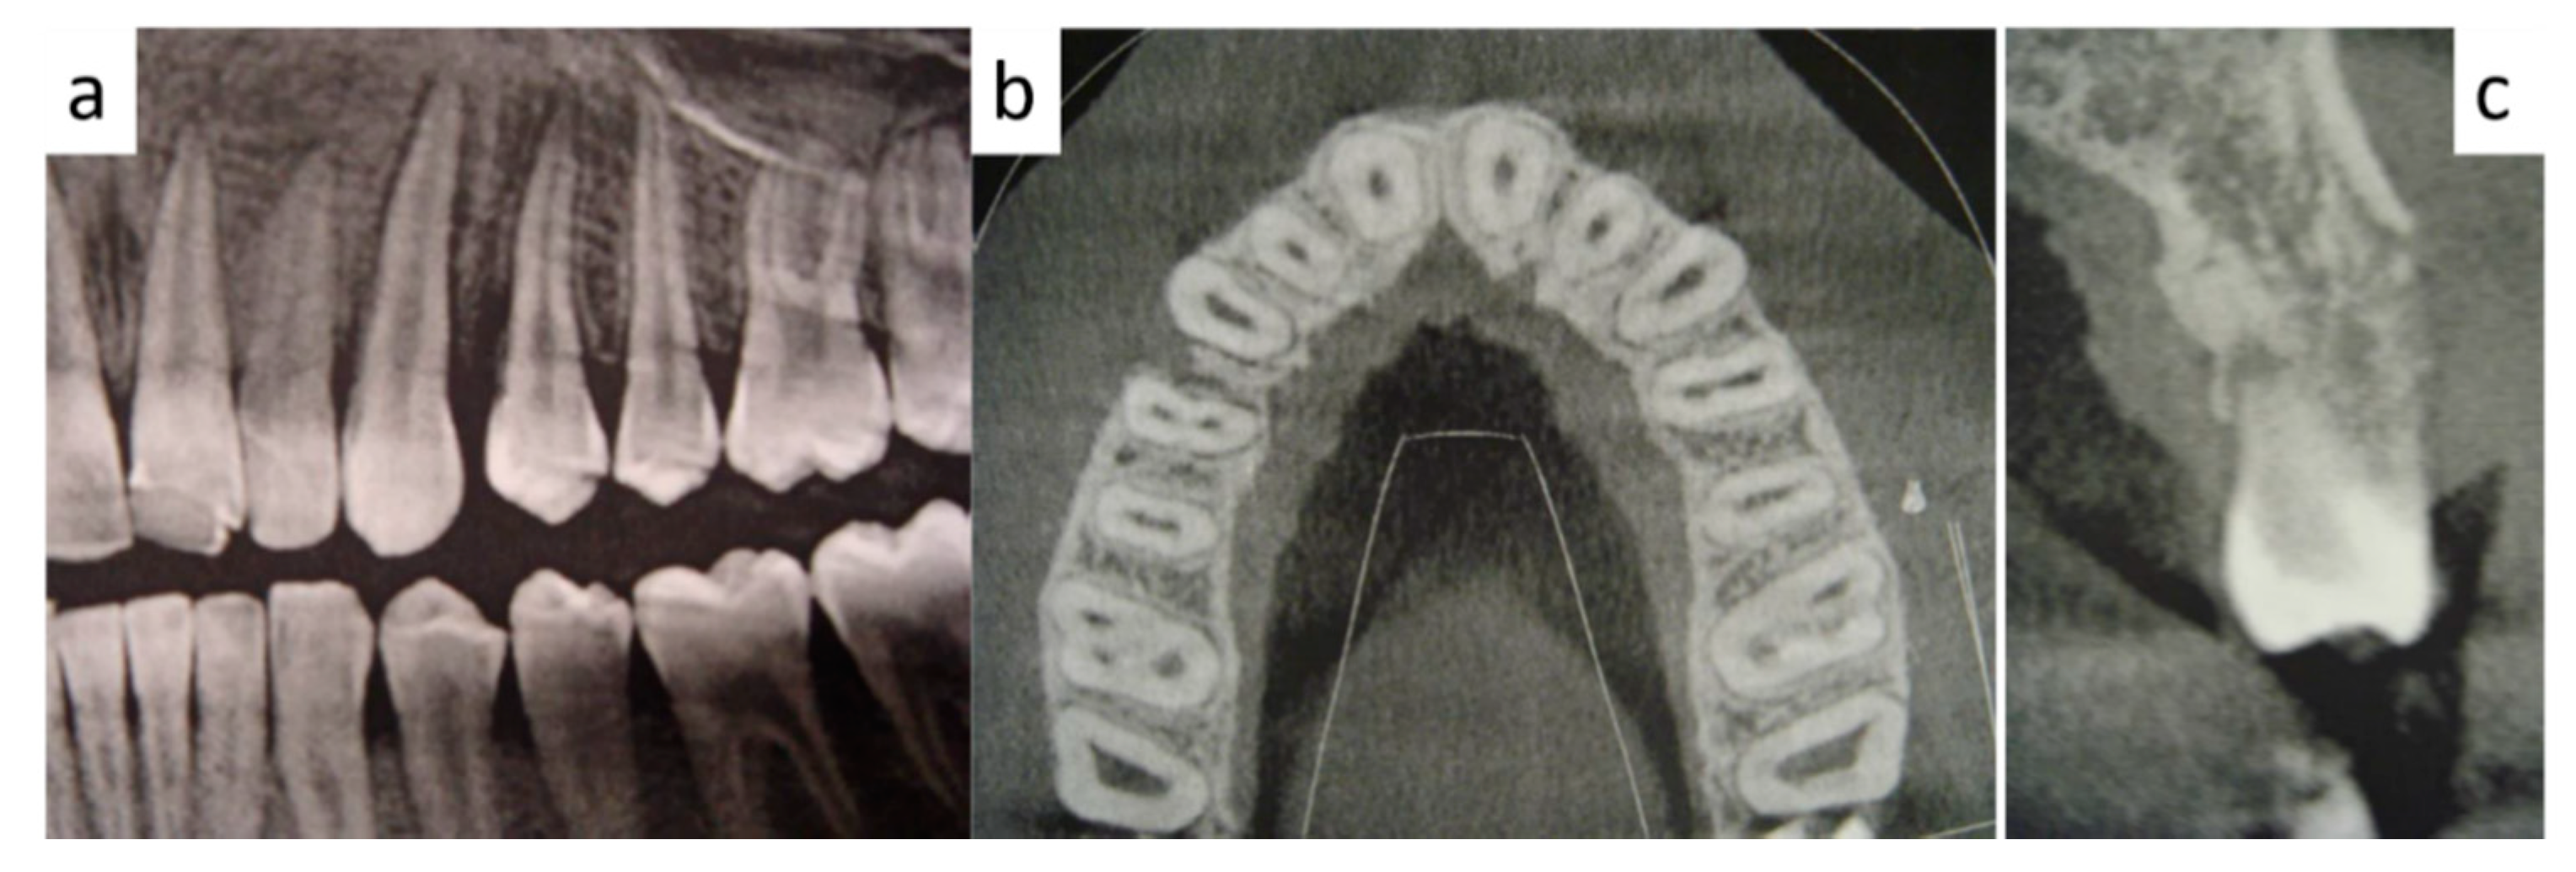

2. Case Presentation